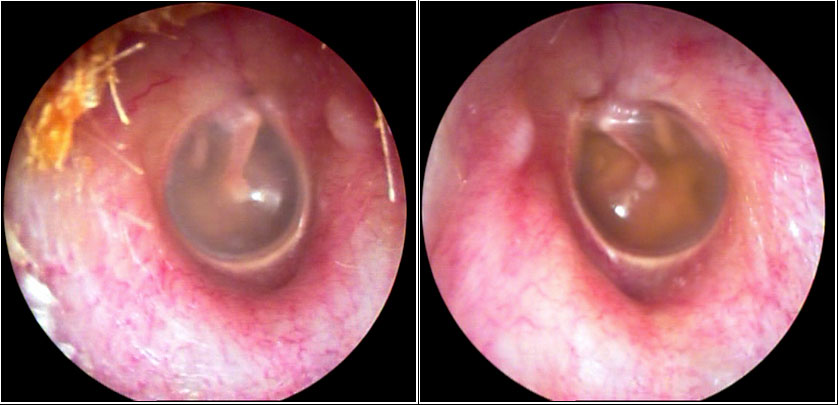

JFC Otitis media serosa.

JFC Otitis media serosa de origen disbárico.

JFC Otitis media serosa izquierda.